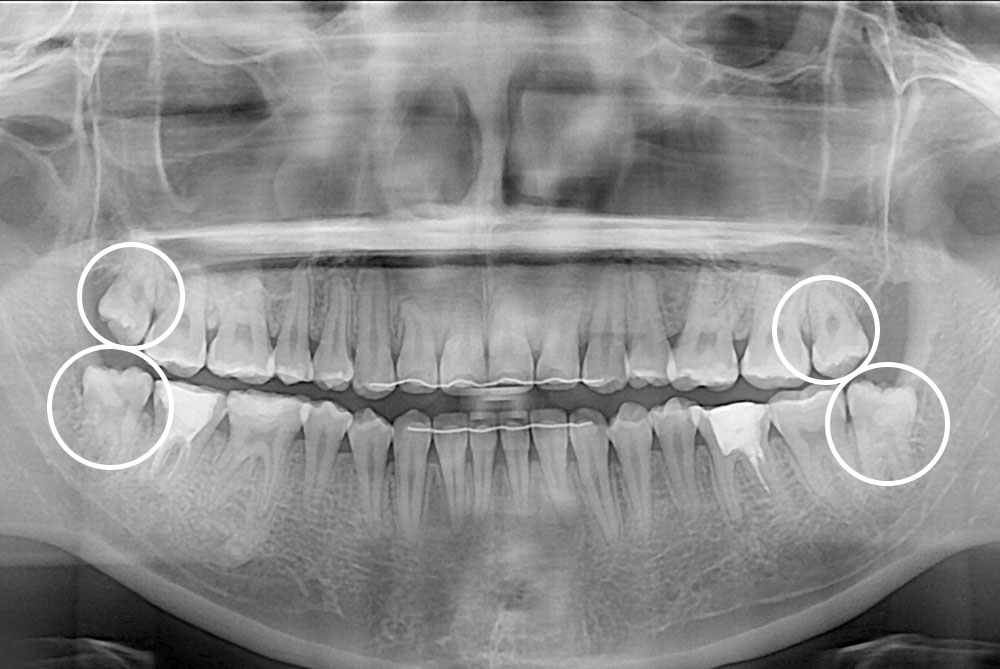

[사랑니] 매복 사랑니 발치

치료후 : 2023-05-09